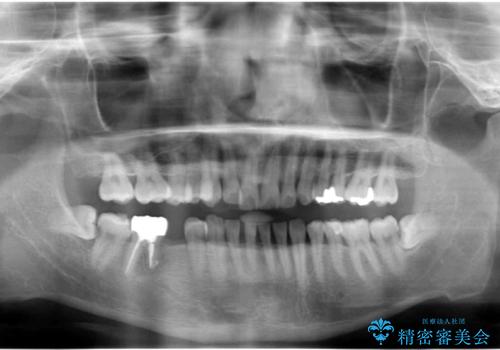

30代女性 前歯のオールセラミック

根管治療は問題なさそうでしたが、質の低いベニヤで修復されていたため、根管への漏洩予防・審美性回復の観点から6前歯をオールセラミックにてやり直すこととなりました。

被せものの種類:ジルコニアオールセラミック クラウン スペシャル